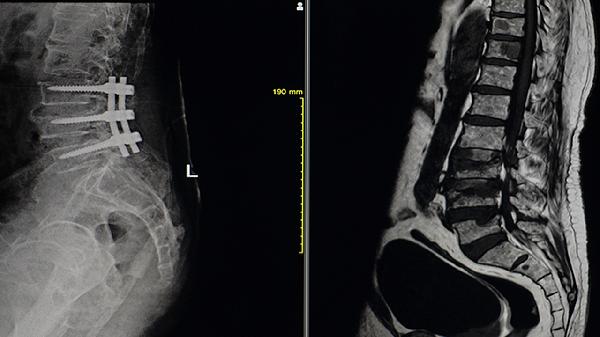

5、手术治疗

严重脊柱畸形患者可能需要全髋关节置换术或脊柱矫形手术。当髋关节完全强直影响行走,或脊柱后凸导致平视障碍时,手术可重建关节功能。术后仍需药物控制炎症,并接受康复训练恢复肌肉力量。手术决策需综合评估疾病活动度和器官功能。